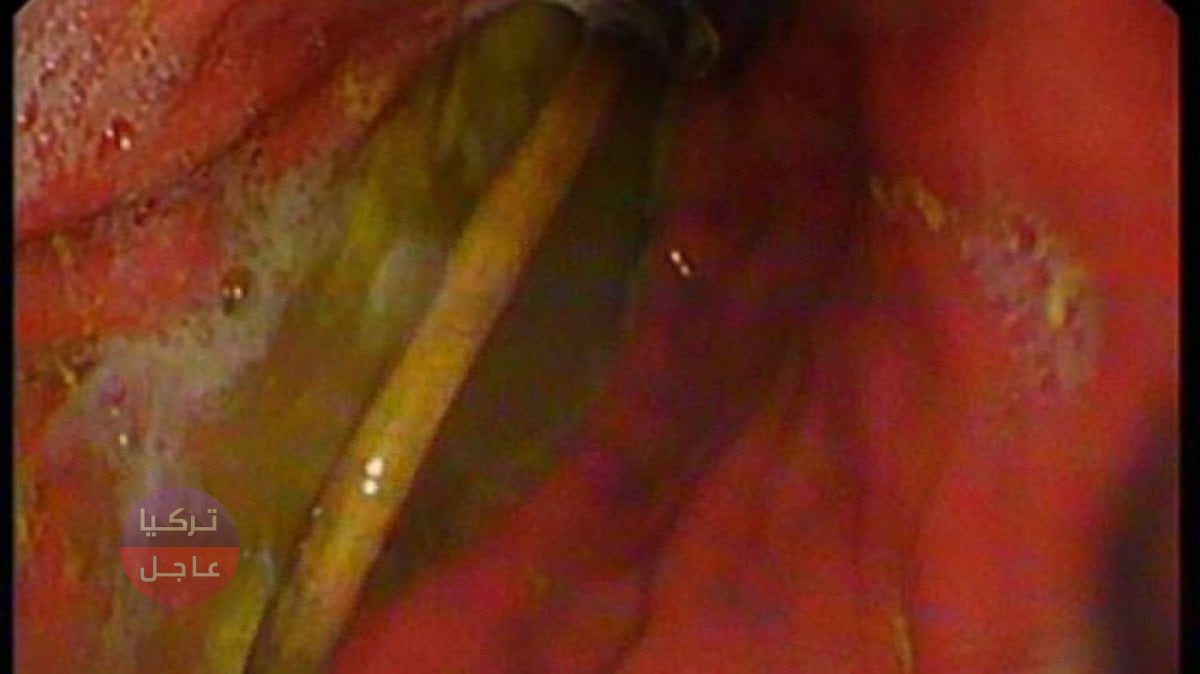

نقلت عائلة تركية في ديار بكر صبيًا يبلغ من العمر 15 عامًا ،كان يعاني من القيء والغثيان ، إلى المستشفى، وتبين وجود مشبك وكابل شحن في معدته.

وبحسب ما نقلته وكالة دوغان التركية، أن الأطباء في المشفى صدموا عندما شاهدوا الصور الشعاعية للكابل الذي انتقل طرفه الى الأمعاء، وتقرر نقل المريض الى آلازيغ بسيارة إسعاف.

وفي مستشفى جامعة فرات في ألازيغ ، أفاد رئيس قسم أمراض الجهاز الهضمي والكبد والتغذية لدى الأطفال، أن الكابل تمت إزالته من خلال عملية بالمنظار قام بها الدكتور يسار دوغان وفريقه.

“أحد طرفي الكابل قد مر إلى الأمعاء الدقيقة”

ونقلت الوكالة عن الطبيب يسار دوغان أنهم واجهوا صعوبة بسبب مرور أحد طرفي الكابل إلى الأمعاء الدقيقة وأدلى بالتصريحات التالية:

تقدم المريض للمؤسسة الصحية بسبب شكاوى من قيء وألم في البطن. تم استشارتنا عندما تم اكتشاف كابل في معدة المريض أثناء الفحوصات التي أجريت هناك. سألونا عما إذا كانوا سيقومون بالإجراء اللازم للمريض أخبرناهم أنه يمكنهم إرسال المريض إلينا.

بعد وصول المريض إلينا ، تم عمل الاستعدادات الأولية ، وبعد فترة الصيام المطلوبة ، خضع المريض لعملية المنظار. حيث تمت إزالة الكابل الموجود في المعدة عن طريق التنظير الداخلي. من الواضح أننا واجهنا صعوبة في إزالة الكابل لأن أحد طرفي الكابل قد مر إلى الأمعاء الدقيقة. بعد اكتمال الإجراء بنجاح ، تم إرسال المريض إلى منزله بصحة جيدة “.